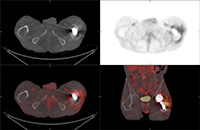

60 year-old man with history of lung cancer and left hip arthroplasty suffered from stiffness in the left hip region. Axial CT, FDG PET, fused axial, and coronal PET-CT demonstrates increased uptake of FDG in heterotopic ossification in the musculature of the left thigh. |